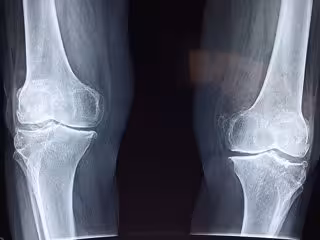

Ventajas de la fisioterapia virtual tras un reemplazo de rodilla

Un estudio llevado a cabo por investigadores de la Universidad de Duke (Estados Unidos), y publicado en 'The Journal of Bone & Joint Surgery', ha evidenciado los beneficios que aporta la fisioterapia virtual a pacientes que se han sometido a una artroplastia de rodilla, un procedimiento quirúrgico que reemplaza la articulación de la rodilla para aliviar el dolor y la discapacidad.

El estudio incluyó a 306 pacientes con una edad media de 65 años y que se habían sometido a un procedimiento de reemplazo de rodilla. Los pacientes fueron asignados aleatoriamente para someterse fisioterapia tradicional, ya sea en el hogar o en visitas a clínicas, o un programa de fisioterapia virtual.